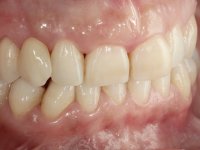

Female patient, 43 years old, non-smoker. Showed an edentulous space in the upper right canine area, resulting from tooth 1.3 impaction. The space had a mesio-distal diameter reduced to the normal size of the upper canine. This is consistent with the presence in the arch of the deciduous canine up to two years ago). Orthopantomography allows clearly view of tooth 1.3 impaction.The patient has a thick gingival phenotype and tolerable oral hygiene.

The proposed treatment results from the limitations imposed by the patient, who refused an orthodontical pull of the canine into the edntulous space, and was unwilling to extract the impacted canine and place an implant in the zone of 1.3. Thus, the confection of a Maryland Bridge was proposed, with a Zr infrastructure and two retainers. The mesial retainer would be bonded to the palatal face of the tooth 1.2 and the distal retainer was to be bonded to the palatal wall of tooth 1.4.